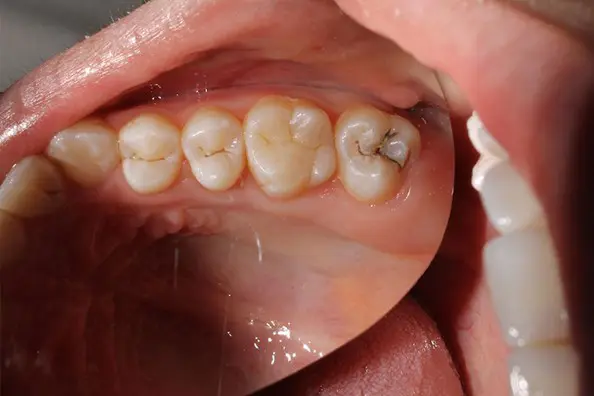

- Cambios de color localizados (amarillo, marrón o grisáceo).

- Manchas oscuras o pequeños agujeros que notas con la lengua.

- En caries moderadas: eliminamos el tejido afectado y restauramos el diente con composites estéticos mediante empastes y reconstrucciones.